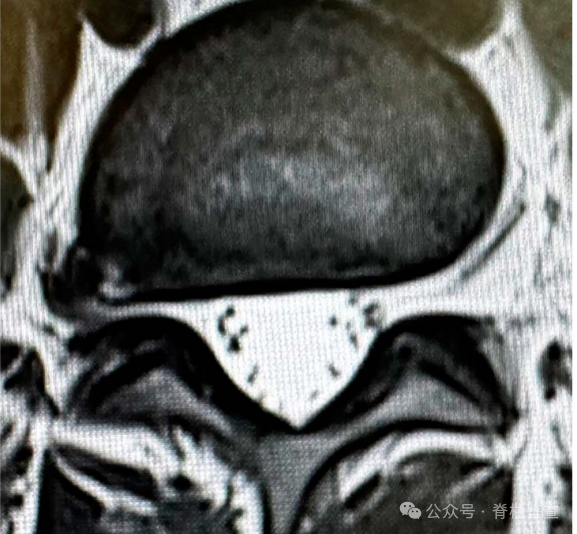

旁外侧腰椎间盘突出,可分为椎间孔型和椎间孔外型,占所有腰椎间盘突出症的0.7-11.7%。常压迫出口神经根和背根神经节,通常会导致严重的疼痛,同时需要特殊手术入路。

以L4-5右侧椎间孔外椎间盘突出为例,对于椎间孔内外减压,必须识别三个骨性标志:上位椎体横突、峡部和下位椎体上关节突。